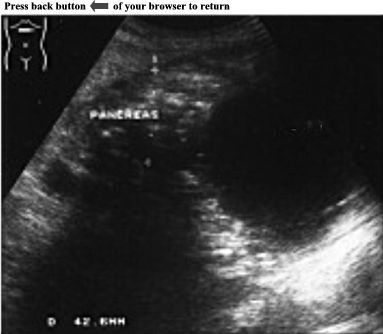

CASE

8:

Examination

of

pancreas

revealed

an

enlarged

head

(5cm)

with

non-homogeneous

parenchyma

and

multiple

calcifications.

Chronic

pancreatitis

was

diagnosed

sonographically.

Further

a

well-defined,

large,

anechoic

mass

in

the

pancreatic

body

tail

(14,6cm

X

10,5cm).

Small

amount

free

fluid

upper

abdomen

observed.

ANSWER:

Pseudocyst